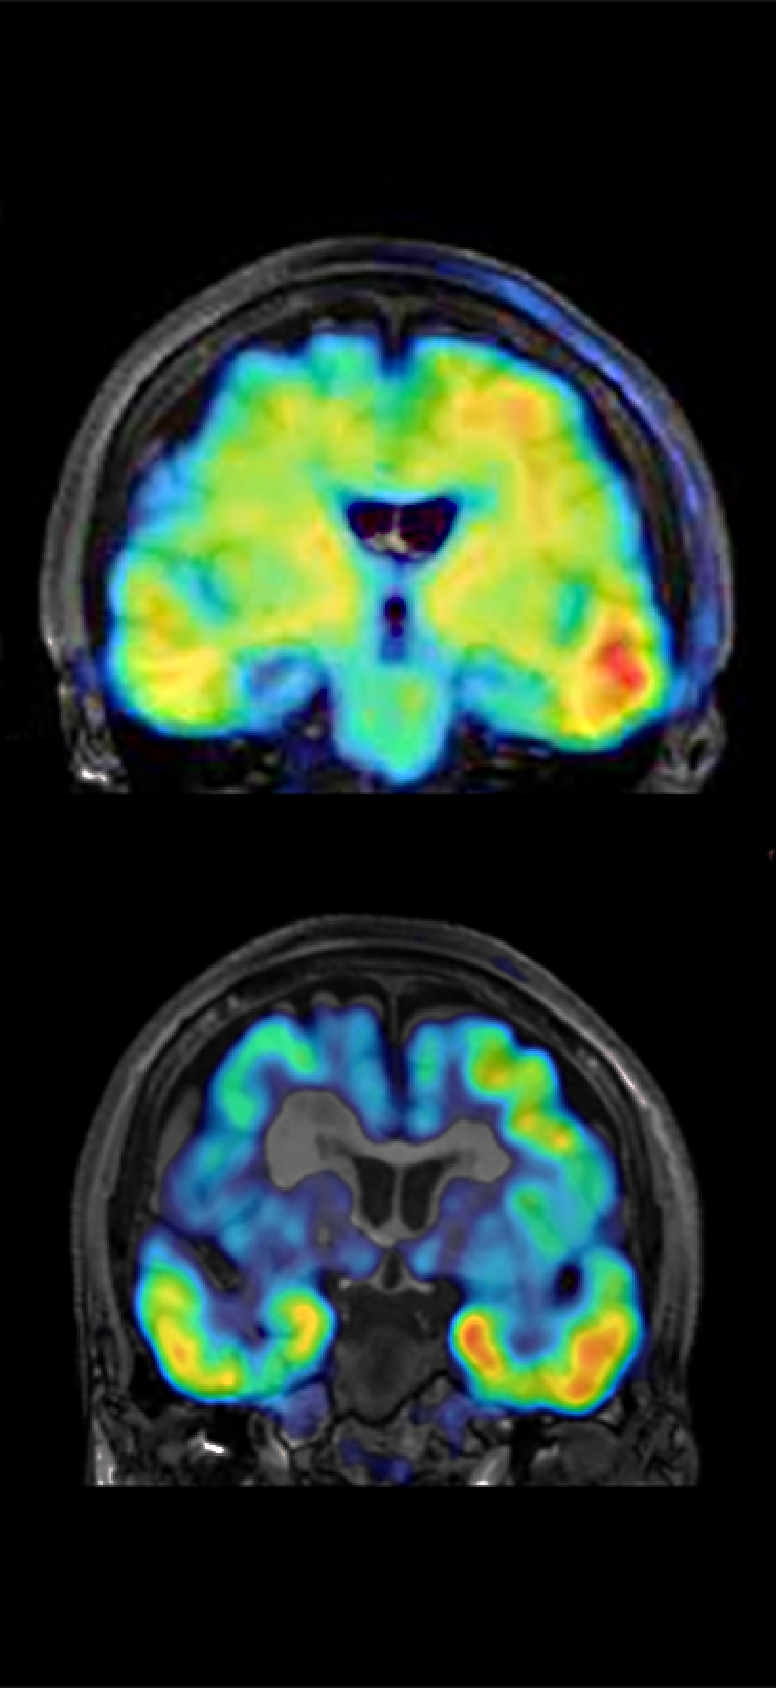

Early detection and modulation of the dementia pathogenesis based on the concept evolving from glial pathology to senoinflammation

さらに、2023年8月に政府が提唱した「認知症・脳神経疾患研究開発イニシアティブ」を受け、ムーンショット目標7の枠組みのもと、認知症克服を目的とした新たな研究が加速しています。2024年11月からは、「脳内セノインフラメーション」を含む3件の新規プロジェクトが本格的に始動しました。